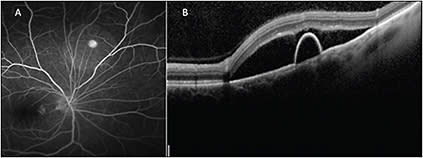

Spectral-domain OCT confirmed both a PED and subretinal fluid. The clinical exam, OCT, and fluorescein angiography were consistent with the diagnosis of peripheral CSR. Targeting the OCT to the area of interest allowed for confirmation of the diagnosis.

The availability of widefield OCT may have allowed for imaging of the PED and optic nerve within the same scan. Targeted OCT allows for improved assessment of stability or progression of the extent of subretinal fluid at follow-up (Figure 2, page 39).

Figure 2. Fluorescein angiography (A) shows a pinpoint area of hyperfluorescence consistent with the diagnosis of CSR. A peripheral targeted SD-OCT B-scan (B) shows both subretinal fluid and a pigment epithelial detachment in a patient with peripheral CSR.